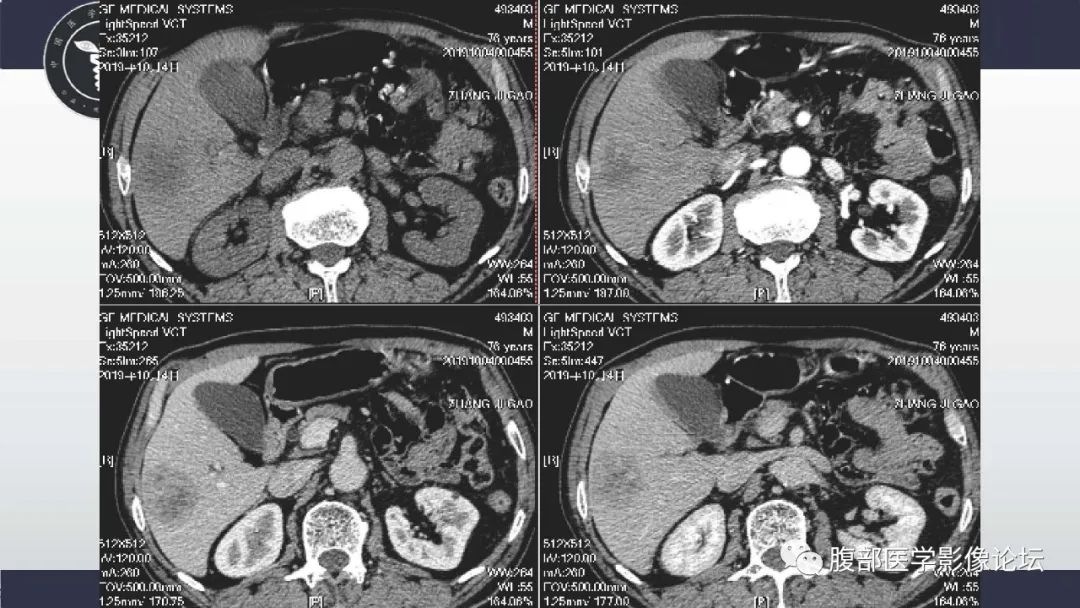

肝脏神经内分泌癌1例CT影像

李广明:病例1肝脏多发占位,部分病灶快进快出,部分渐进强化,延迟似乎可见包膜,左叶病灶可以一血管影 。疾病谱神经内分泌癌,淋巴瘤,胆管细胞癌,转移瘤。病灶延迟部分有环状强化 不太支持胆管细胞癌,强化方式也不符合一般转移瘤。有血管穿行需要考虑淋巴瘤,但动脉期这种强化方式不常见,神经内分泌影像表现符合。综合考虑神经内分泌癌>淋巴瘤,建议核磁检查。 医学百科网 | YxBaike.Com

向前相后:1.病灶多发,肝左叶病灶内可见血管影,强化中度,包膜不明显,老年人,先排除转移,在排除淋巴瘤,最后排除神经内分泌肿瘤。 医学百科网 | YxBaike.Com

陈应东:肝脏多发占位,边界不清,增强渐进强化,延迟期稍低于肝,内部血管穿行,密度较均匀,考虑淋巴瘤,鉴别nets,囊变坏死多见;icc不符合点无邻近包膜凹陷,无中央简质延迟强化。转移瘤:需要原发肿瘤病史。IMT:周围多有一过性灌注,容易囊变坏死,强化程度不一。 医学百科网 | YxBaike.Com

赵绍武:肝内多发肿块,部分血管穿行,强化不一,考虑神经内分泌肿瘤,鉴别淋巴瘤,转移瘤 医学百科网 | YxBaike.Com

:肝脏多发占位,部分病灶快进快出,部分渐进强化,延迟似乎可见包膜,左叶病灶可以一血管影 。疾病谱神经内分泌癌,淋巴瘤,胆管细胞癌,转移瘤。病灶延迟部分有环状强化 不太支持胆管细胞癌,强化方式也不符合一般转移瘤。有血管穿行需要考虑淋巴瘤,但动脉期这种强化方式不常见,神经内分泌影像表现符合。综合考虑神经内分泌癌>淋巴瘤,建议核磁检查。 医学百科网 | YxBaike.Com

Self:肝脏多发肿块,增强轻度强化,内见血管穿行,考虑淋巴瘤。

罗晓红:老年男性,肝右叶下段病灶为多发小囊样改变,猜个ICC。IMT、神经内分泌待排!! 医学百科网 | YxBaike.Com

影子:老年男性,肝内多发病灶,低至中度强化,动脉期有血管穿行征,静脉期与延迟期有晕征,优先考虑EHE,需要同转移瘤(缺乏靶征与其他部位原发恶性肿瘤病史,实验室检查无特殊,不太支持)与淋巴瘤(强化不均匀,脾脏不大,未见到淋巴结增大等不支持)。